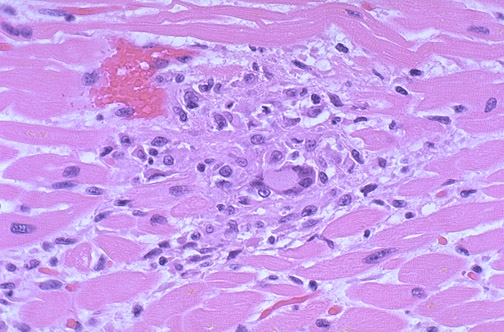

Межуточный миокардит: гистологические исследования

Раздел: Идеи и советы